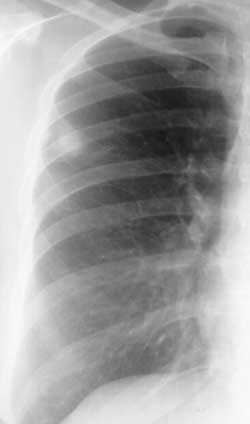

Рис. 4. Аденокарциома. Интенсивная, однородная тень с четкими бугристыми, "лучистыми" контурами и тяжем к плевре.